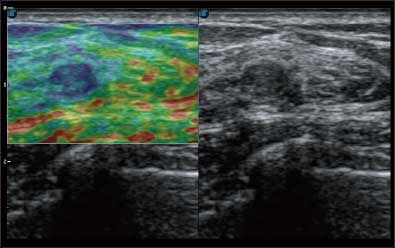

通过对组织运动信息、血流信号及背景噪声进行准确智能的阈值判定,高效提取出微弱血流信号,获得高灵敏度和空间分辨率的血流图像,为临床提供更加真实和丰富的诊断信息。

全新算法处理射频信号 不可靠区域自动剔除 支持定量分析 压力曲线保证重复性